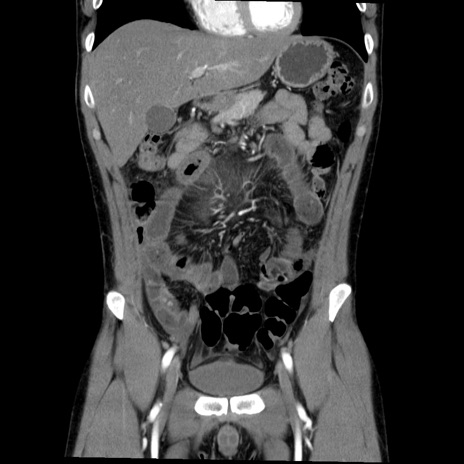

症例36(冠状断像)

【症例】20歳代 男性

【主訴】心窩部痛

【現病歴】今朝より上腹部痛あり。一旦軽快していたが再度出現したため救急要請。昨日夕に白身の魚を含む刺身を食べた。

【身体所見】BP 136/89mmHg、HR 74/min、BT 37.0℃、腹部:膨満、軟、心窩部に圧痛あり。反跳痛なし、筋性防御なし、腸雑音やや亢進あり。

【データ】WBC 17700、CRP 0.48